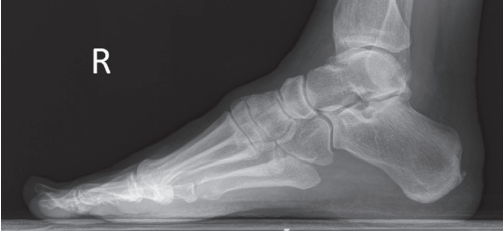

The medial talar dome is demonstrated anterior to the lateral talar dome

Over-rotated/ external rotation

The medial talar dome is demonstrated posterior to the lateral talar dome

Under-rotated/ internal rotation

Medial talar dome is anterior to the lateral dome

Fibula is more posterior

Foot is externally rotated

Medial talor dome is posterior to the lateral dome

Foot is internally rotated

The lateral talar dome is proximal to the medial dome, the height of the medial longitudinal arch appears less than it actually is, and the talocalcaneal joint is narrowed.

Proximal lower leg has been elevated